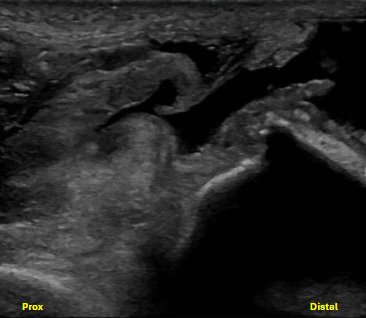

Short axis view of the distal triceps tendon stump demonstrating loss of normal fibrillar structure of the triceps tendon. There is also anechoic and hypoechoic fluid signal, compatible with hematoma or seroma formation.

Unlabeled short axis view at the level of the distal humerus proximal to the olecranon fossa, evaluating the triceps tendon/muscle with evidence of bony avulsions.

Labeled short axis view of the distal triceps tendon stump showing loss of normal fibrillar structure of the triceps tendon, with discrete bony avulsions within the retracted triceps tendon. There is anechoic and hypoechoic fluid signal, compatible with hematoma or seroma formation.